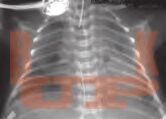

Сурфактант в неонатологии. Профилактика и лечение респираторного дистресс-синдрома новорожденных

Фундаментальное и практическое руководство по профилактике и лечению РДС. Детальный разбор всех препаратов, методов респираторной поддержки и их интеграции в комплексную терапию на основе доказательной медицины. Для неонатологов, акушеров, педиатров и реаниматологов

В книге представлен систематический обзор современных представлений о системе сурфактанта, позволяющий читателю понять связь между состоянием этой системы, биофизическими процессами в альвеолах новорожденного, физиологическими особенностями дыхания, патофизиологическими механизмами дыхательных нарушений и принципами их коррекции.

Приведена информация о биохимии, физиологии и фармакологии сурфактанта, детально характеризуются все препараты сурфактанта, применяющиеся в клинической практике.

Особое внимание уделено клиническим аспектам диагностики, профилактики и лечения респираторного дистресс-синдрома у недоношенных новорожденных с позиций доказательной медицины. Детально изложены вопросы практического применения препаратов сурфактанта в различных клинических ситуациях, причем применение сурфактанта рассматривается не как изолированный метод лечения, а как составная часть комплексного подхода. Подробно описаны различные методы инвазивной и неинвазивной респираторной поддержки, приведено патофизиологическое обоснование их дифференцированного применения.